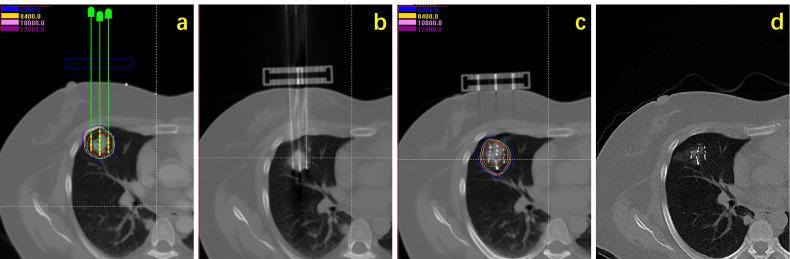

To analyze the efficacy and safety of low dose rate stereotactic ablative brachytherapy (L-SABT) for treatment of unresectable early-stage non-small cell lung cancer (NSCLC).

Data of patients with early-stage NSCLC who received CT-guided L-SABT (radioactive I-125 seeds implantation) at eight different centers from December 2010 to August 2020 were retrospectively analyzed. Treatment efficacy and complications were evaluated.

方法

回顾性分析2010年12月至2020年8月在八个不同中心接受CT引导下L-SABT(放射性I-125粒子植入)的早期NSCLC患者的数据。评估治疗疗效和并发症。